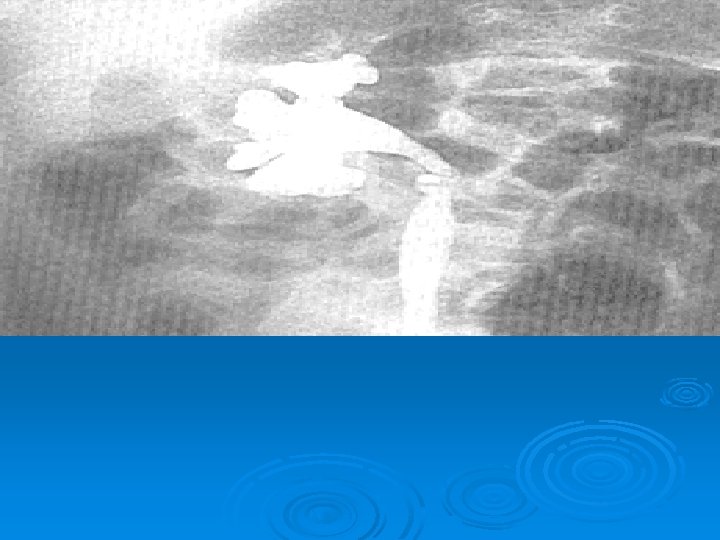

Çocukluk Çağında İdrar Yolu Enfeksiyonları İZLEMDE TANISAL GÖRÜNTÜLEME YÖNTEMLERİ Ø Miksiyon sistoüretrografisi: Vezikoüreteral geri kaçış (VÜR) görüntülenir. Ø DMSA sintigrafisi: Skar görüntülenir. Ø IVP: Tıkanıklık görüntülenir. Ø DTPA sintigrafisi: Tıkanıklık, böbrek fonksiyonları bozuk hastalarda atılım fonksiyonlarını değerlendirilebilir.